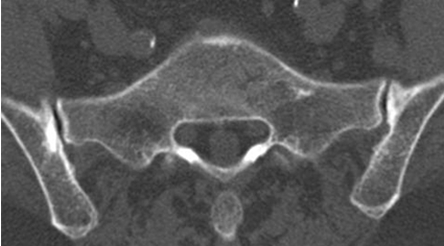

Fig 8. Fenómeno del vacío.

TAC axial, con presencia de aire en ambas SI y esclerosis asociada.